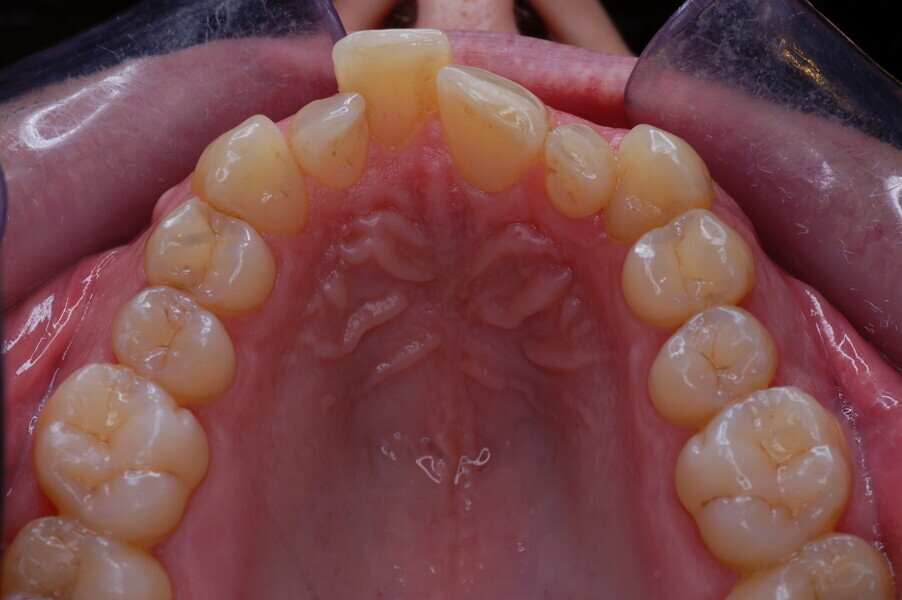

A healthy 39-year-old man presented to our orthodontic office with the chief complaint of an unattractive dental appearance and fear of the orthognathic surgery proposed by another orthodontist. Clinically, the patient’s profile was straight, and the frontal view did not show any facial asymmetry. The functional examination did not reveal any mandibular deviation or reduced movements. The patient had no joint pain, and no joint noise was observed.

Figs. 1–8: Pretreatment facial and intra-oral photographs.

From the periodontal point of view, the patient showed a good attitude to oral hygiene, but crowding of the mandibular incisors made cleaning difficult in that area, causing plaque accumulation and localised gingival inflammation. The panoramic radiograph revealed the presence of the mandibular third molars and confirmed the absence of the mandibular right central incisor (Fig. 10).

The cephalometric analysis showed a skeletal Class II malocclusion (convexity of Point A: 4.9 mm), a slightly retruded chin position (facial depth: 78.1°) and a skeletal open bite tendency (lower facial height: 53.19°; facial axis: 80.58°; Fig. 9). The mandibular incisors were lingually tipped (Li–APog: 9.3°) and retruded (Li–APog: 1.55 mm), and there was an increased inter-incisal angle of 142.9°.